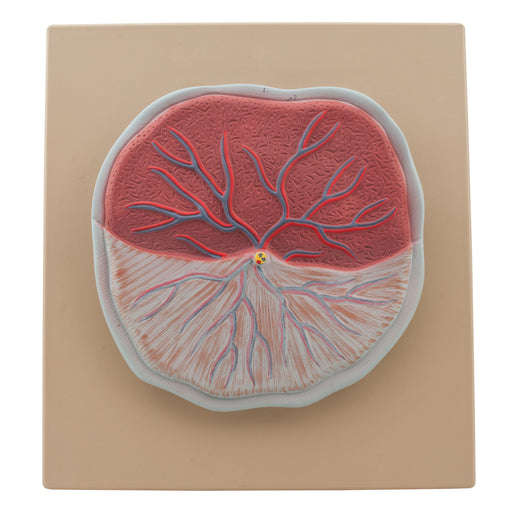

Placenta

This model of placenta showing all important parts. Mounted on base. Supplied with English Key Card. Size 35 x 33 x 6 cm approx. Weight 855 g approx.